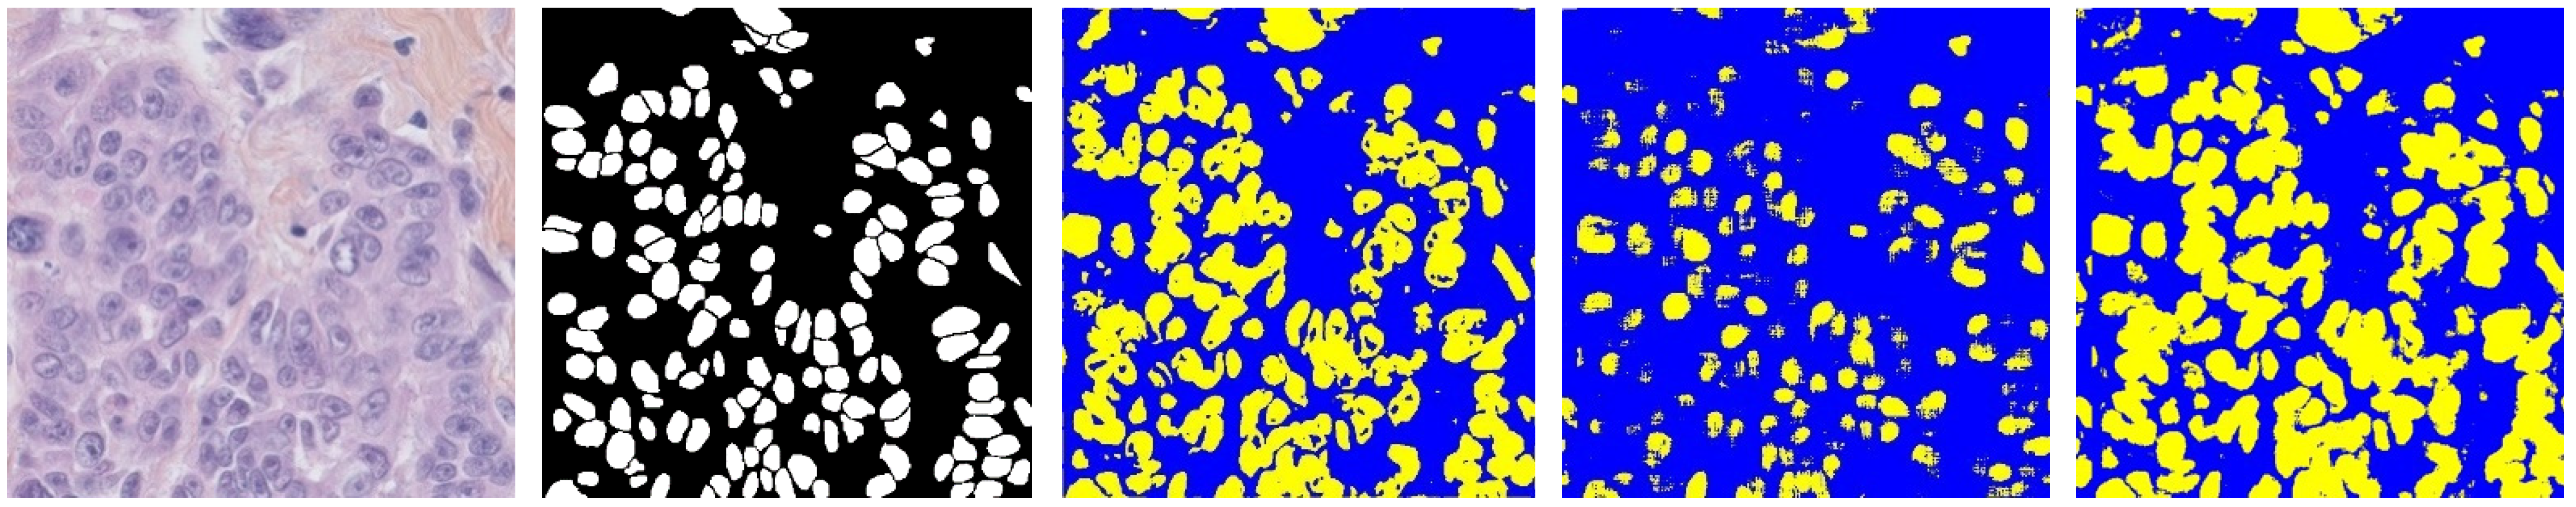

3.2. Segmentation Based on Improved U-Net

Experimental Tests